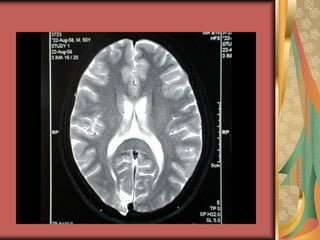

OPTIC RADIATIONS

The corresponding retinal elements

lie progressively closer, so

congruous hemianopia.

Passes through the temporal lobe

and pareital lobe and ends in the

visual cortex.